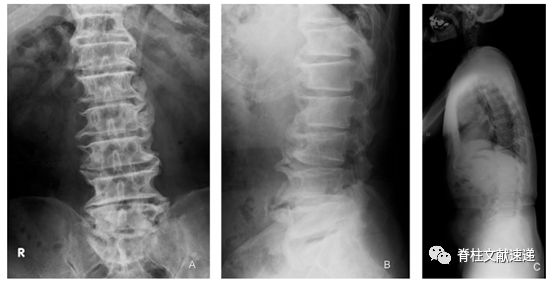

图注:一位83岁合并DISH病的LSS患者的术前X线片,可以明显观察到脊柱前侧新生骨桥的形成